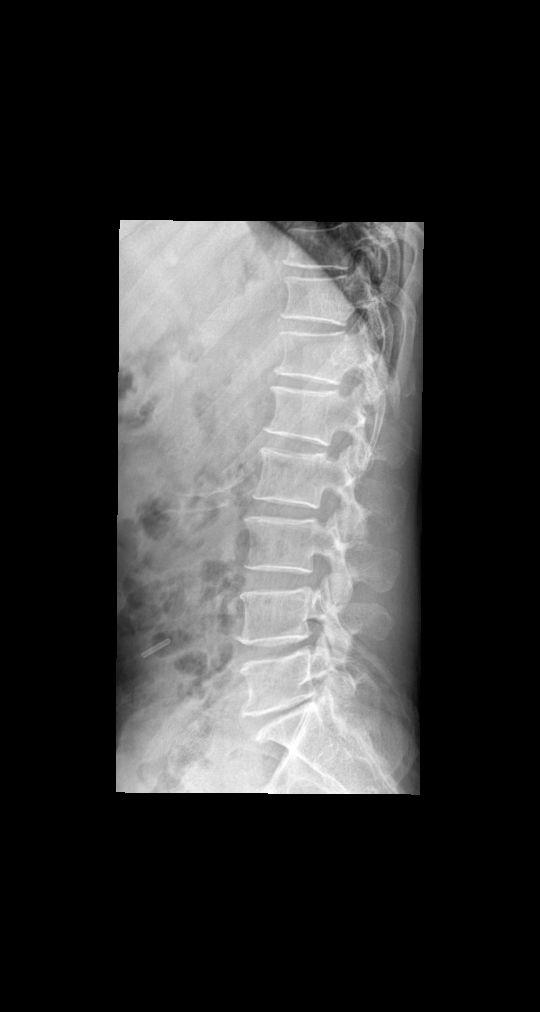

男 55 腰部疼痛就诊